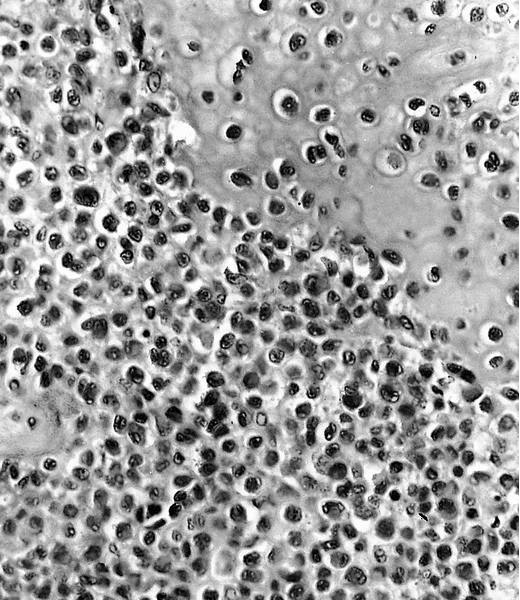

Microscopic (histologic) description

- Composed of round or polyhedral chondroblasts with abundant eosinophilic cytoplasm and well defined cell borders; spindle shaped cells may be focal (Ann Diagn Pathol 2003;7:205, Cancer 1972;30:401)

- Nuclei are oval, hyperlobulated with grooves

- Pericellular lace-like or chicken wire type calcification among degenerative chondroblasts

- Chondroid matrix almost always present (pink rather than blue matrix)

- May have marked cellularity, intracytoplasmic glycogen granules, mitotic figures, necrosis and osteoclast type giant cells

- No significant nuclear atypia as compared with malignant chondroblastoma (Mod Pathol 2020;33:2295)

Microscopic (histologic) images

Cytology description

- FNA demonstrates clusters of uniformly round to oval cells with loose matrix and scattered multinucleated giant cells (Cancer Cytopathol 2018;126:552)

An 18 year old man presents with a 3 cm, well defined lucent lesion within the epiphysis of the distal femur. Microscopic features of the surgical curettage specimen are represented by the H&E images. The best diagnosis is

A. Chondroblastoma. Chondroblastomas commonly present in the second decade of life as a singular, well defined lucent lesion within skeletally immature long bones. Characteristic histopathological features include sheets of chondroblasts admixed with osteoclast-like giant cells in a chondroid matrix and focal chicken wire type calcification. Chondroid fibromas typically lack chicken wire type calcification. Chondroblastoma-like osteosarcomas generally display an infiltrative growth pattern with marked cytologic atypia. Chondroid matrix is not commonly seen in giant cell tumor of bone.